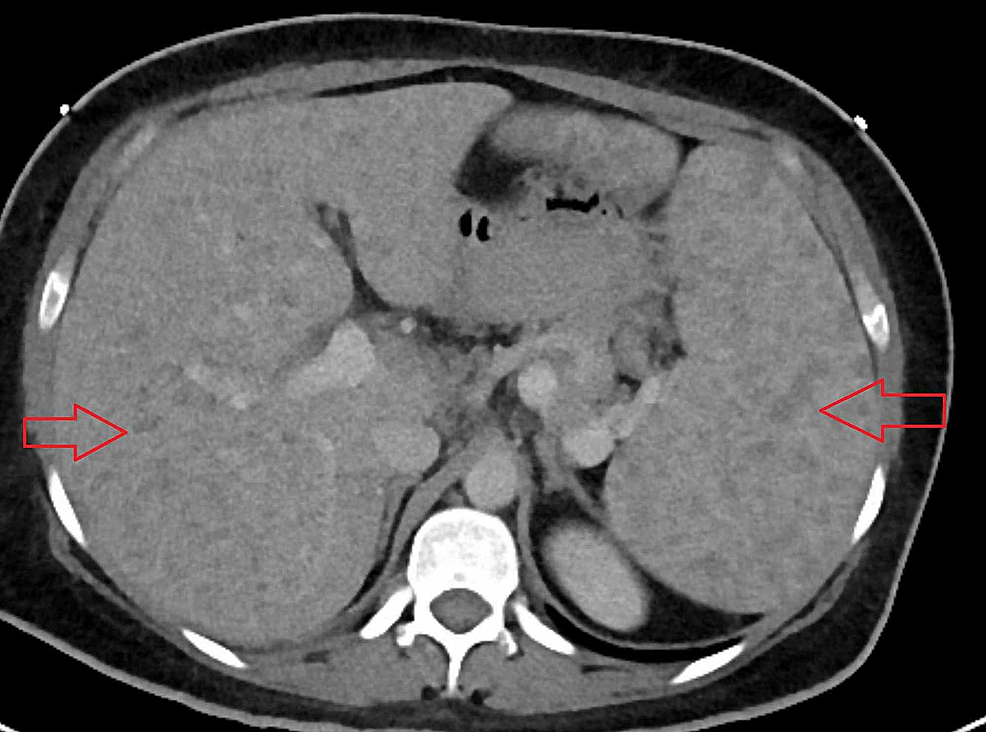

Cureus A Rare Case of Necrotizing Sarcoid Granulomatosis Involving Liver Symptoms Of Liver Granuloma hepatic granulomas are localized collections of inflammatory cells, which are found in 2% to 10% of patients. Hepatic granulomas have numerous causes and are usually asymptomatic. Granulomas themselves typically cause no symptoms. hepatic granulomas are small, localized areas of inflammation that form in the liver. Hepatic granulomas have numerous causes and are usually. Clinical features reflect the underlying. Symptoms Of Liver Granuloma.

Cureus A Rare Case of Necrotizing Sarcoid Granulomatosis Involving Liver Symptoms Of Liver Granuloma Clinical features reflect the underlying systemic disease and its. although most granulomas are harmless and do not cause symptoms, they can sometimes lead to liver damage or. Hepatic granulomas have numerous causes and are usually asymptomatic. hepatic granulomas may be found incidentally on an otherwise normal liver biopsy or may be caused by. hepatic granulomas are small,. Symptoms Of Liver Granuloma.